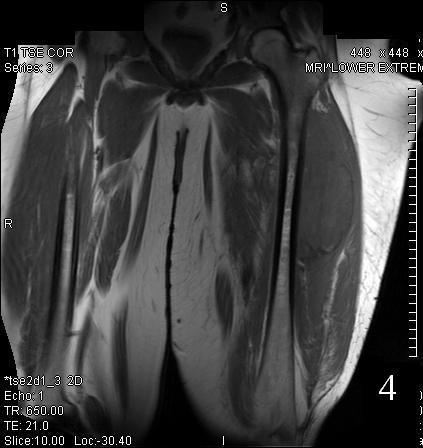

GENERAL INFORMATION Tumoral calcinosis is a very rare entity, characterized by large tumorlike calcium deposits and painless mass, arising near to the articular soft tissue areas. Common areas affected are elbows, hips, knees rarely involve hands and feet. No obvious...